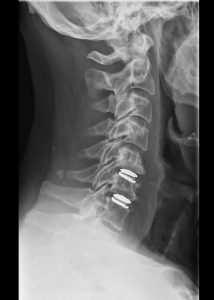

Η τοποθέτηση τεχνητού δίσκου έχει σαν στόχο να διατηρήσει την κίνηση των σπονδύλων και να αποτρέψει την εκφύλιση σε άλλα επίπεδα του αυχένα. Η διαδικασία είναι παρόμοια με την κλασσική πρόσθια αυχενική δισκεκτομή (ACDF), ωστόσο, αντί για έναν σταθερό κλωβό, τοποθετείται ένας τεχνητός δίσκος, δηλαδή ένα εμφύτευμα που διατηρεί την κίνηση (Εικόνα 1).